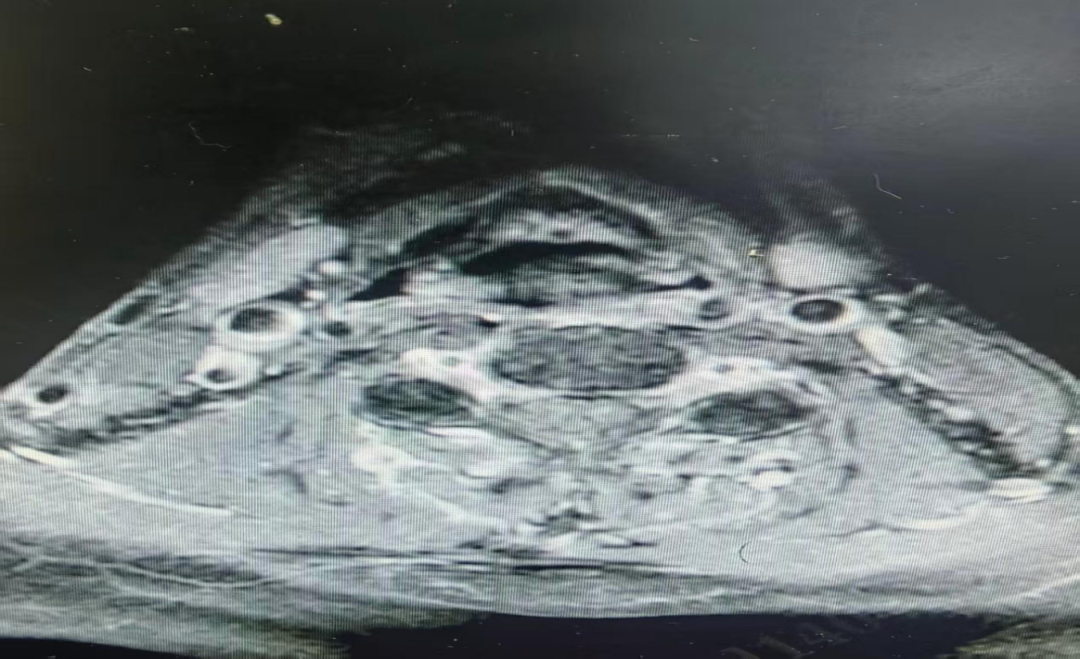

患者通过“一站式住院”快捷办理入院,住院医师刘璇与上级医师黄准迅速为李伯伯安排了喉部核磁共振增强检查。结果指向了一个罕见的诊断:左梨状窝血管瘤。

图片